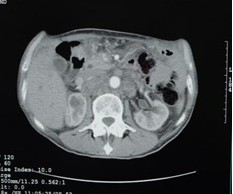

女,40歲,2006年10月底確診為胃腺癌(皮革胃),腹腔淋巴結(jié)轉(zhuǎn)移;2006年11月外科手術(shù)時(shí)見(jiàn)腹腔廣泛轉(zhuǎn)移(粘連),病灶無(wú)法切除(下圖1a,b),預(yù)期生存期低于3個(gè)月;留置(胃)造瘺管。2006年12月開(kāi)始今又生聯(lián)合化療治療,今又生2×1012VP,室溫下自行融化后加入到100ml生理鹽水中,30~40分鐘內(nèi)靜脈滴注完畢,1/次/周,連續(xù)使用6周。今又生給藥三天后靜脈化療。2007年7月外科手術(shù)拔除造瘺管;2007年9月隨訪,患者狀況良好,無(wú)復(fù)發(fā)。

1a 治療前胰腺體部和主動(dòng)脈前方淋巴結(jié)較多較大,胃底和體部較厚僵硬

1b治療后 淋巴結(jié)較少并縮小,胰腺和主動(dòng)脈之間脂肪間隙恢復(fù)清晰,胃底和體部較前變薄,柔軟

2a 治療前 主動(dòng)脈前方,胃底和脾門(mén)之間見(jiàn)大量結(jié)節(jié)狀淋巴結(jié)

2b 治療后 主動(dòng)脈前方,胃底和脾門(mén)之間淋巴結(jié)大部分消失縮小,脂肪間隙較前清晰